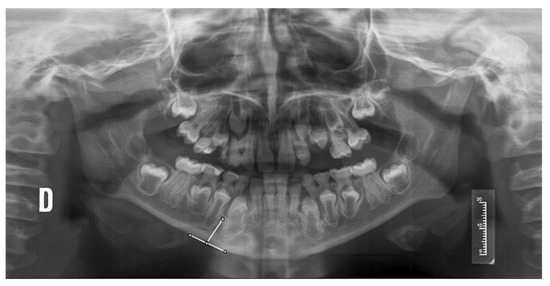

- Mandibular cortical width (MCW), measured from a tangential to the mandibular border and another parallel to the ascending ramus, obtaining a tangent through the mental foramen (Figure 1).